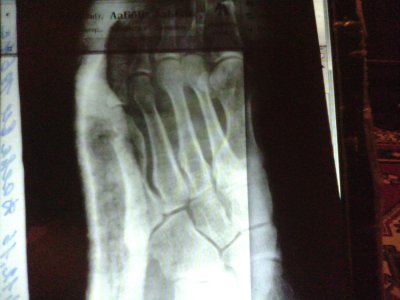

• 20161129_093741.jpg

20161129_093741.jpg

115,3 КБ · Просмотры: 275